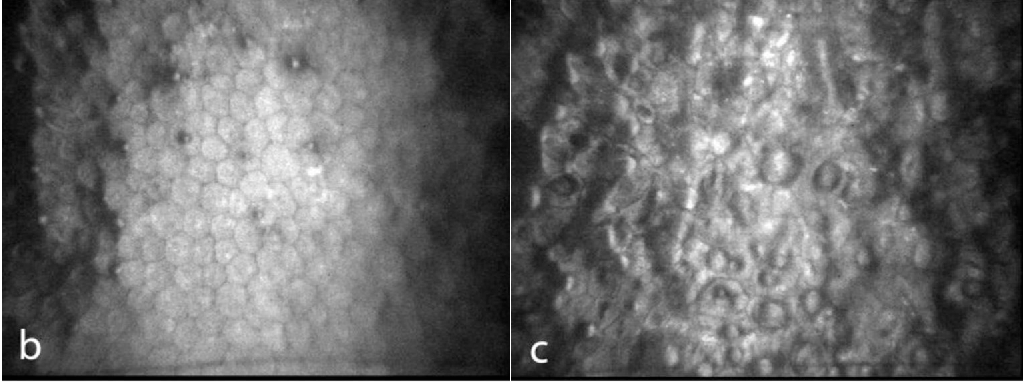

각막내피세포에 구타타(Guttata)가 관찰되고,

정상적인 각막내피세포가 구타타로 뒤덮이면서,

서서히 정상적인 유효한 각막내피세포수가 감소하면서 시작됩니다.

이때 각막모양이 Beaten bronze 혹은 Beaten metal 이라 하여,

두드린 놋쇠 혹은 두드린 금속과 같은 모양이라고 합니다.